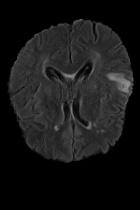

Current unsupervised anomaly localization approaches rely on generative models to learn the distribution of normal images, which is later used to identify potential anomalous regions derived from errors on the reconstructed images. However, a main limitation of nearly all prior literature is the need of employing anomalous images to set a class-specific threshold to locate the anomalies. This limits their usability in realistic scenarios, where only normal data is typically accessible. Despite this major drawback, only a handful of works have addressed this limitation, by integrating supervision on attention maps during training. In this work, we propose a novel formulation that does not require accessing images with abnormalities to define the threshold. Furthermore, and in contrast to very recent work, the proposed constraint is formulated in a more principled manner, leveraging well-known knowledge in constrained optimization. In particular, the equality constraint on the attention maps in prior work is replaced by an inequality constraint, which allows more flexibility. In addition, to address the limitations of penalty-based functions we employ an extension of the popular log-barrier methods to handle the constraint. Comprehensive experiments on the popular BRATS'19 dataset demonstrate that the proposed approach substantially outperforms relevant literature, establishing new state-of-the-art results for unsupervised lesion segmentation.